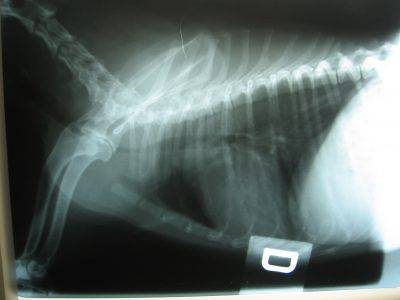

È causata dalla compressione del midollo spinale, di solito alla fine del collo. Nonostante la compressione parta dal collo, sono le zampe posteriori ad esserne colpite. L’andatura può trasformarsi da instabile a traballante, mentre nel caso grave diventa quasi paralisi.

Le vertebre, a causa della pressione del collo, possono deformarsi e comprimersi. Tale compressione danneggia i nervi che trasmettono informazioni agli arti causando conseguentemente paresi (debolezza) o paralisi degli stessi. Inizialmente, la pressione influisce sulla capacità del cane di muoversi normalmente.

All’inizio l’instabilità vertebrale non si avverte quasi per niente. La mancata coordinazione può sollecitare oltremodo i dischi intervertebrali. Alla fine se i dischi si rompono, il midollo avrà delle sollecitazioni eccessivi e verrà danneggiato irreversibilmente. Ciò può tradursi nell’insorgenza improvvisa di paralisi.